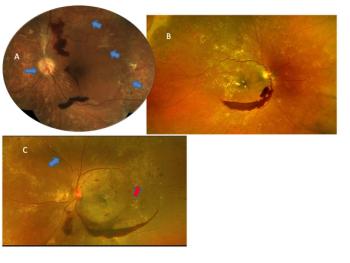

ODs must pay close attention and manage all factors responsible for disease progression to improve the patient’s final outcome. The patient in this case report shows the importance of such management.